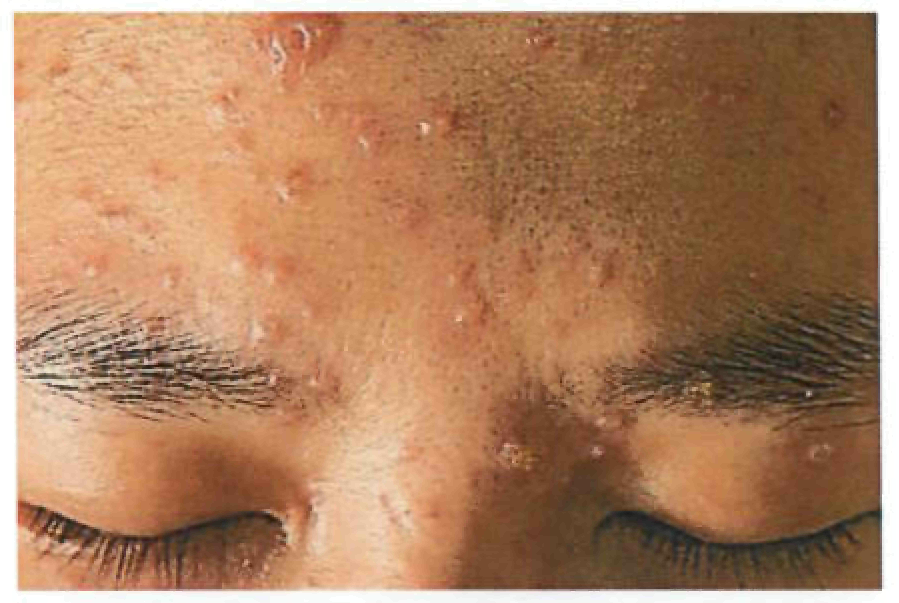

Период высыпаний

На 3-4-й день болезни температура тела снижается до субфебрильной, одновременно на коже головы (прежде всего на лице) и на слизистых оболочках полости рта, гениталий, конъюнктивы, роговицы глаз появляются необильные элементы сыпи. Энантема на слизистых оболочках полости рта обычно предшествует появлению экзантемы. Первые элементы сыпи обычно появляются на лице, быстро распространяясь на верхние конечности, а затем - на туловище и нижние конечности, поражая ладони и подошвы. Распространение экзантемы имеет центробежный характер - на туловище элементов меньше, чем на лице и конечностях.

Высыпания эволюционируют через стадии:

- макула (пятно) (1-2 дня);

- папула (узелок) (1-2 дня);

- везикула (пузырек, заполненный прозрачной жидкостью) (1-2 дня);

- пустула (гнойничок) с пупковидным вдавлением в центре (5-7 дней);

- корочка (7-14 дней).

В 70-80% случаев сыпь характеризуется мономорфностью, в остальных случаях может отмечаться полиморфизм [38]. На одном участке кожи сыпь всегда мономорфна.

В 95% случаев сыпь поражает лицо, в 75% - ладони и подошвы, что является отличительным признаком заболевания. Также поражаются слизистые оболочки полости рта (в 70% случаев), половые органы (30%), конъюнктива и/или роговица (20%). У части пациентов имеет место проктит с поражениями перианальной области изолированно или в сочетании с высыпаниями в области гениталий [39]. Количество элементов сыпи варьирует от единичных до нескольких тысяч [13].